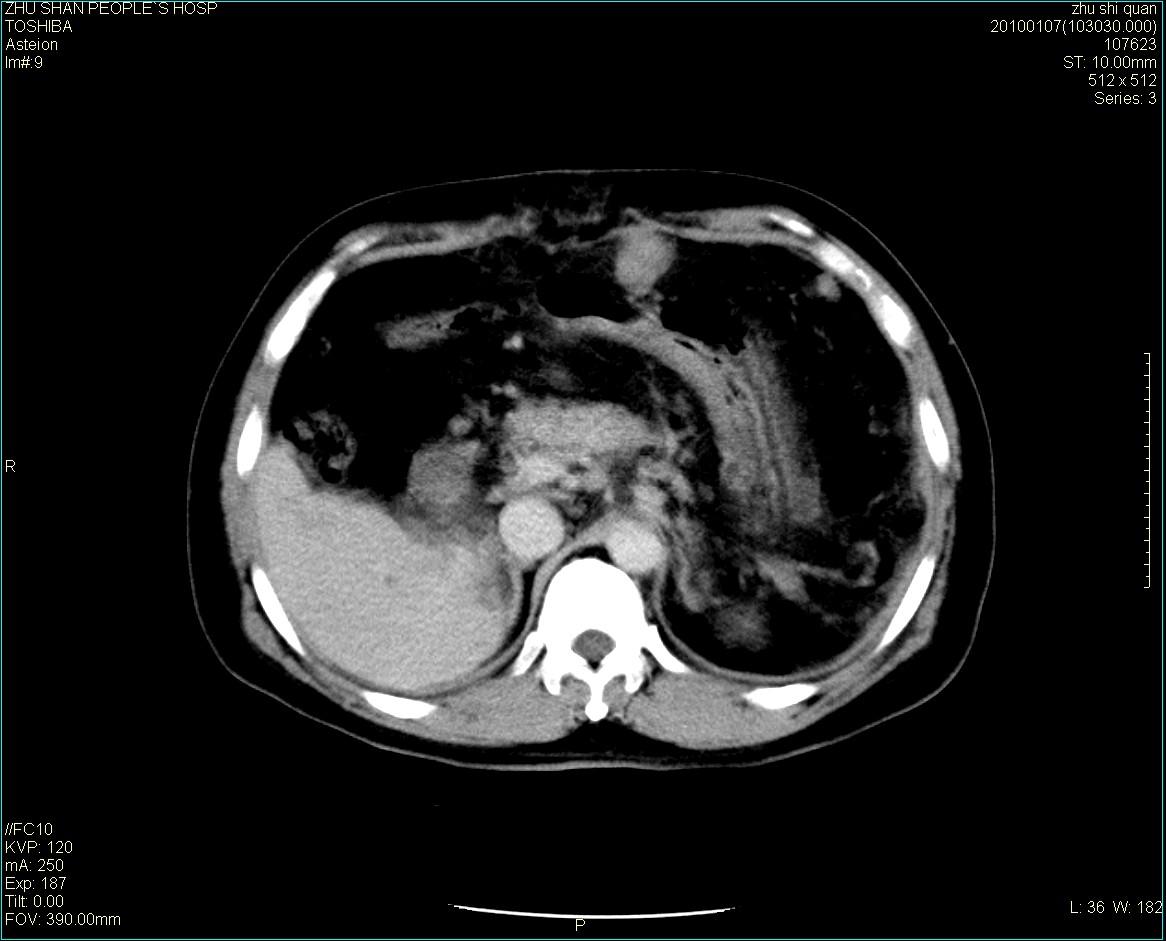

男性病人 肝ca两次术后,今日复查。

多发转移

肝、脾多发转移灶,胸腔积液

1)肝癌并多发性转移。2)双侧胸腔积液(以左侧为甚)伴左下部分肺萎陷。

肝癌术后复发,考虑肝、脾多发转移。

肝癌术后复发,肝内、脾脏、腹膜后及腹膜多发转移,腹水,双侧胸腔积液(以左侧为甚)伴左下膨胀不全。

肝、脾多发转移灶,胸腔积液。

肝癌术后复发,肝内、脾脏、腹膜后及腹膜多发淋巴结转移,腹水,双侧胸腔积液。